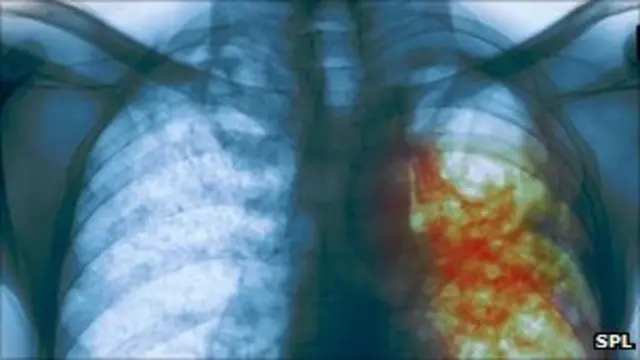

السل المقاوم للأدوية ينتشر بمعدل خطر في أوروبا

حذرت منظمة الصحة العالمية من انتشار حالات السل المقاوم للأدوية بمعدل ينذر بالخطر في جميع أنحاء أوروبا.

وأظهرت تقديرات المنظمة أن هناك نحو 81 ألف إصابة بالسل في اوروبا كل عام لا تستجيب للعلاج بالمضادات الحيوية.